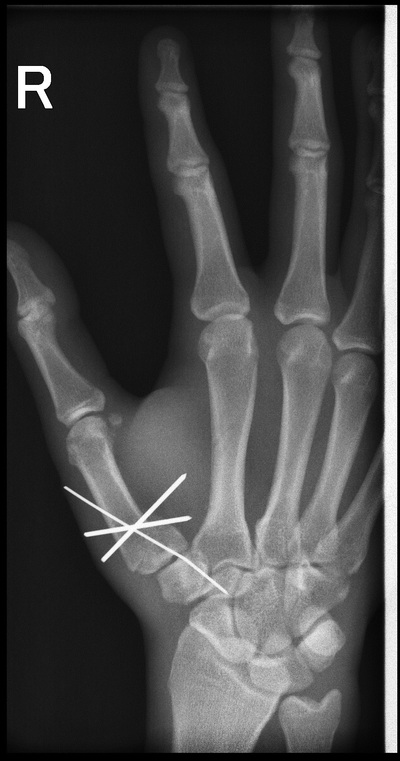

Утро травматолога

за 15 минут до конца дежурства:(

играл в футбол и упал на отведенную руку

нет одну. два снимка